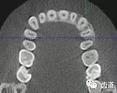

二)牙槽骨外科

CBCT在牙槽骨外科手術(shù)中,通過立體影像可以全面了解牙齒周圍的解剖結(jié)構(gòu),牙根的位置,下頜神經(jīng)管的走向和范圍,上頜竇底的位置及上下牙牙根與上頜竇的關(guān)系,下牙牙根與下頜神經(jīng)管的位置關(guān)系,手術(shù)時就會“有的放失”,采用更加安全的方法,避免損傷上頜竇和下牙槽神經(jīng)。

1、上頜尖牙阻生

上頜尖牙埋伏阻生在CBCT中的影像

2、下頜磨牙阻生

下頜第二第三磨牙阻生口腔曲面斷層片影像

下頜第二第三磨牙阻生CBCT影像定位

三種圖片的影像學(xué)比較